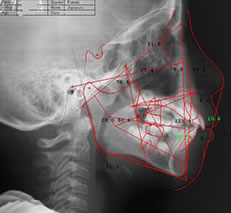

当院では、矯正治療専門のレントゲン機器「セファロ」を導入しています。歯や顎だけでなく、頭全体を正面と横から撮影できます。この撮影データから、歯をどのように動かすのか詳しく判断できるので、治療の精度が高まります。